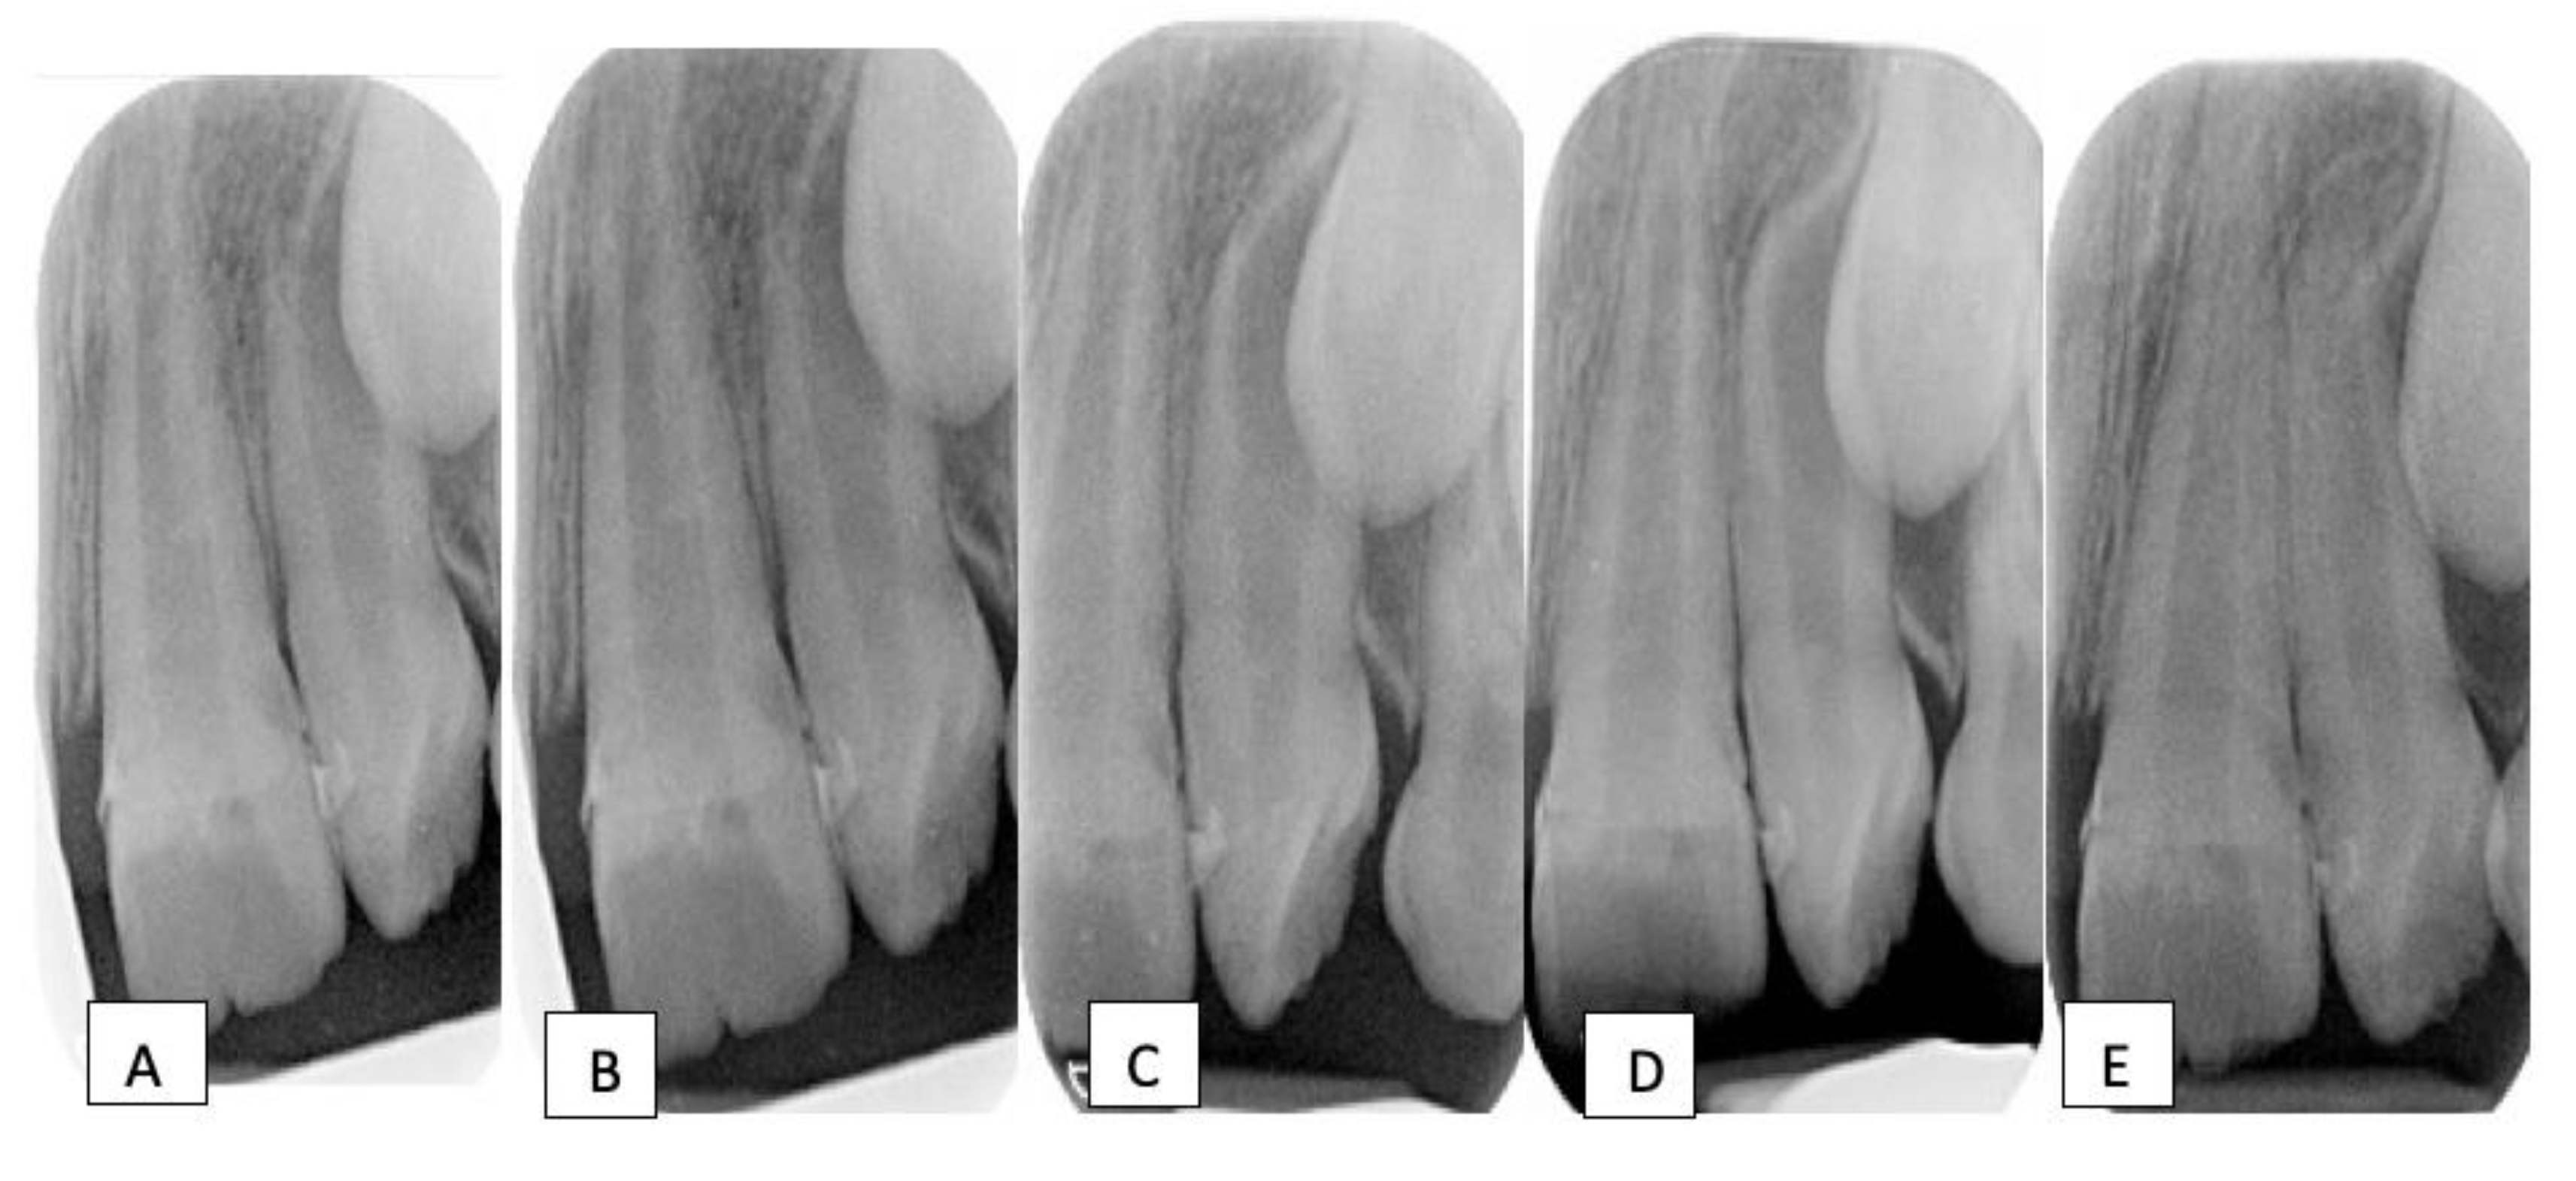

Traumatic intrusion of primary teeth and its effects on the permanent What Is Tooth Intrusion Avulsion, intrusion, extrusion, lateral luxation, alveolar. This force pushes the teeth deeper into the. Intrusive luxation (intrusion) is the displacement of the tooth into the alveolar bone along the axis of the tooth and is accompanied by comminution or fracture of the alveolar socket. The following dental injuries in the permanent dentition require splinting: American academy of pediatric dentistry. Intrusion. What Is Tooth Intrusion.

Figure 1 from Management of intrusion in primary tooth with fixed What Is Tooth Intrusion American academy of pediatric dentistry. Intrusive luxation (intrusion) is the displacement of the tooth into the alveolar bone along the axis of the tooth and is accompanied by comminution or fracture of the alveolar socket. Extraction is indicated if the intruded tooth is impinging on a developing permanent tooth bud. Intruded primary incisor following a traumatic injury. This force pushes. What Is Tooth Intrusion.

Figure 2 from Unusual ectopic eruption of a permanent central incisor What Is Tooth Intrusion This force pushes the teeth deeper into the. American academy of pediatric dentistry. The following dental injuries in the permanent dentition require splinting: Avulsion, intrusion, extrusion, lateral luxation, alveolar. Intrusion of teeth describes a situation where teeth get pushed inwards due to impact or trauma. Intrusive luxation (intrusion) is the displacement of the tooth into the alveolar bone along the. What Is Tooth Intrusion.

Management options for the traumatised, intruded incisor in a growing What Is Tooth Intrusion Intrusion of teeth describes a situation where teeth get pushed inwards due to impact or trauma. Avulsion, intrusion, extrusion, lateral luxation, alveolar. Extraction is indicated if the intruded tooth is impinging on a developing permanent tooth bud. Intrusive luxation (intrusion) is the displacement of the tooth into the alveolar bone along the axis of the tooth and is accompanied by. What Is Tooth Intrusion.